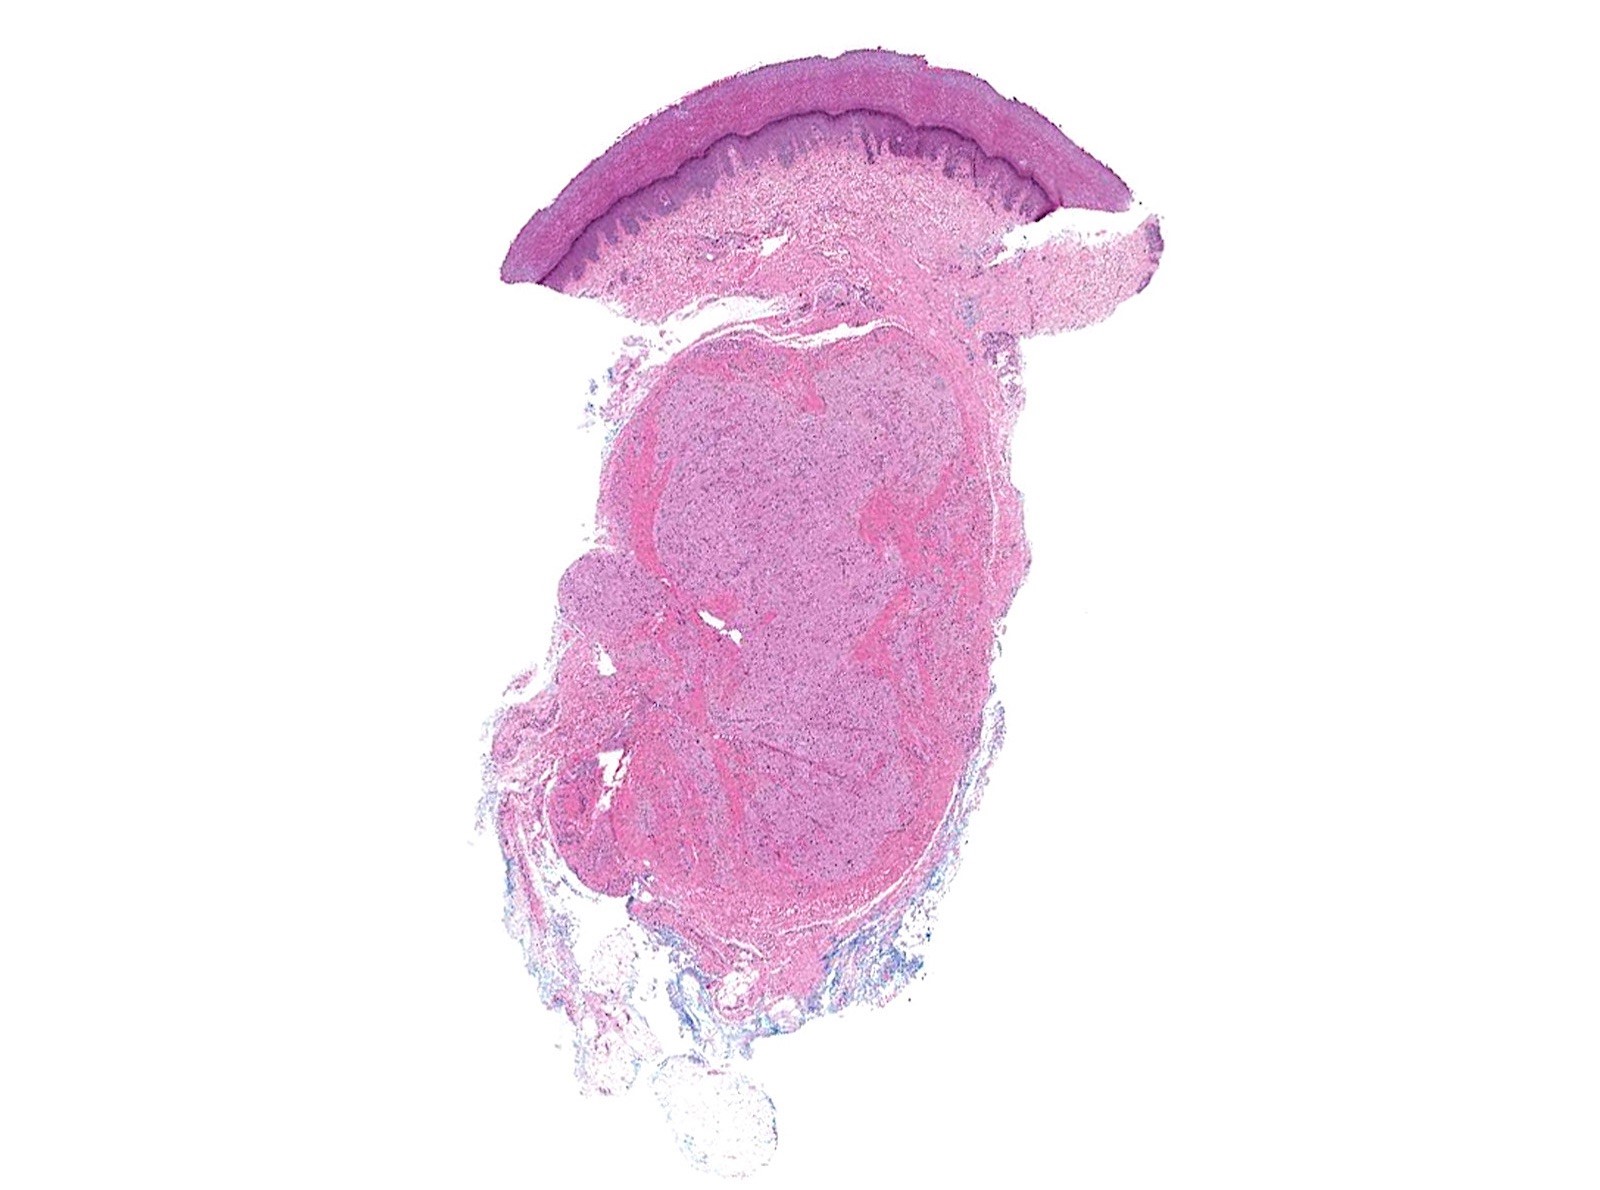

Gross description

- Grayish white to pale yellow

- Oftentimes, not well circumscribed

Gross images

Microscopic (histologic) description

- Infiltrative or circumscribed architecture

- Can involve the subcutis